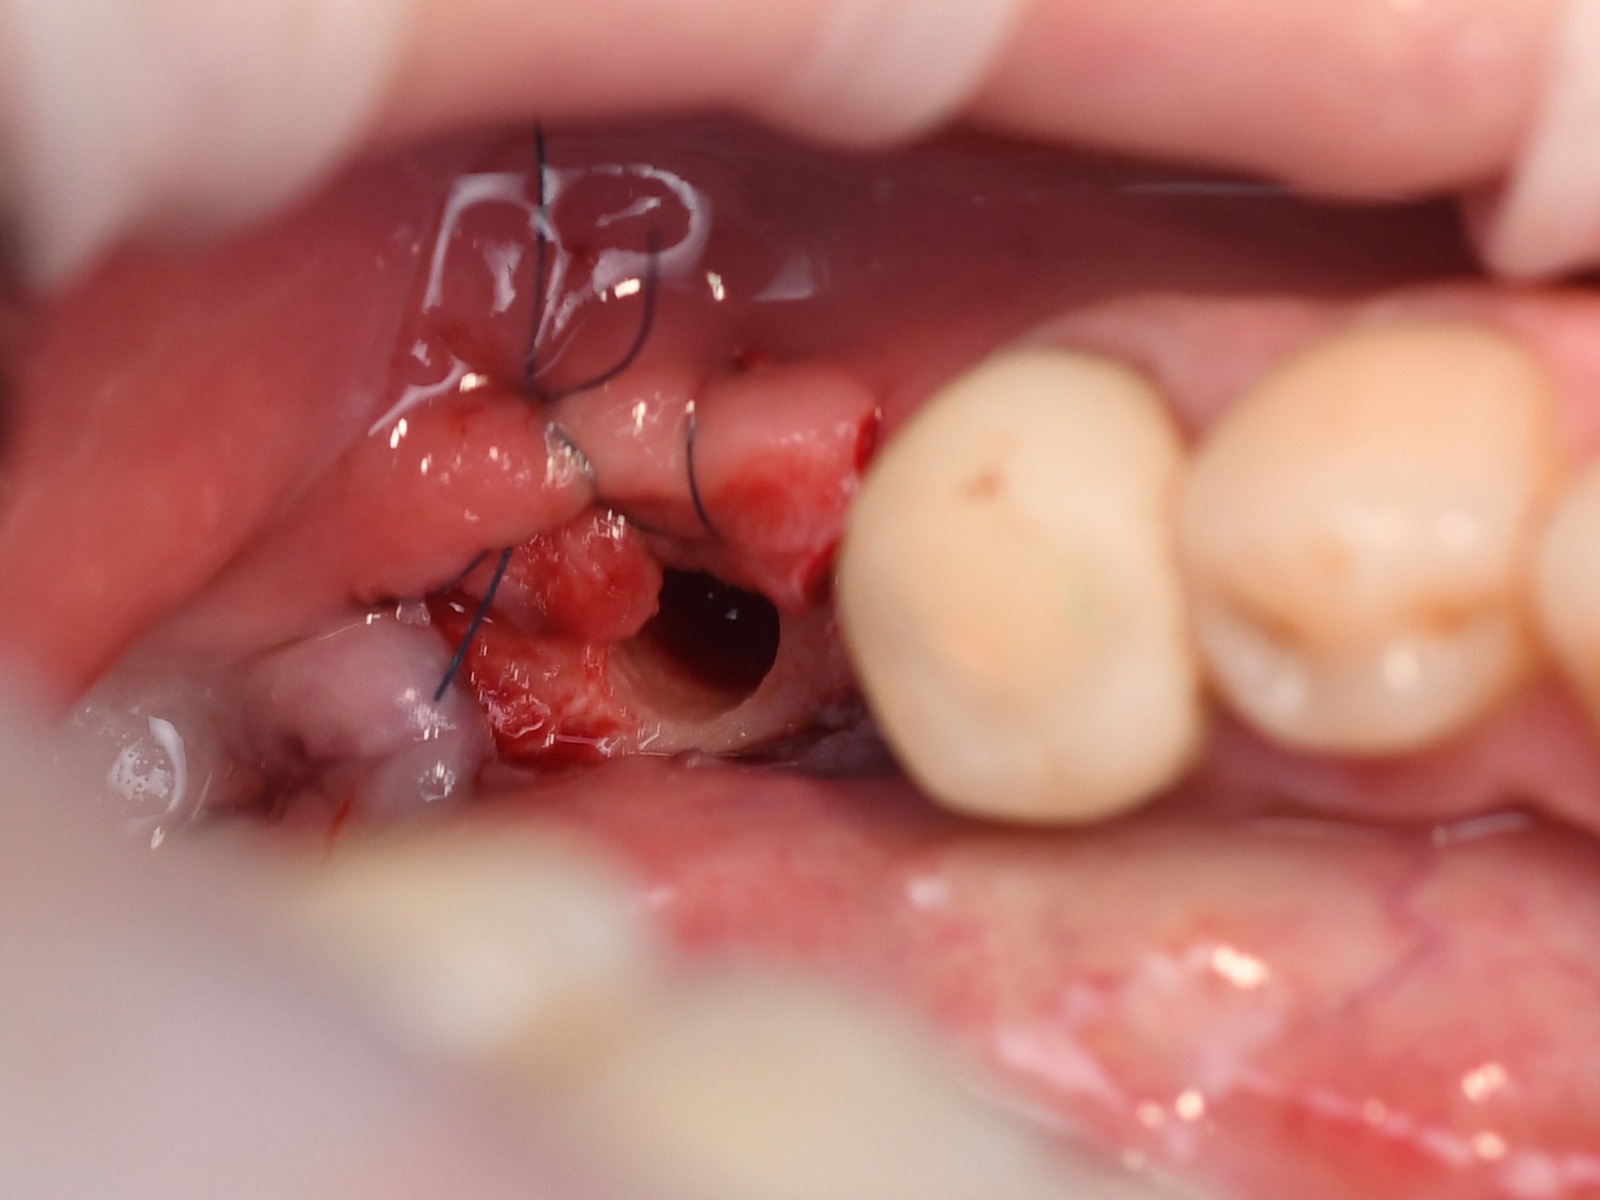

Initial clinical picture

Incision

flap is thinned out of the split thickness

Flap is reflected

The view on the placed implant